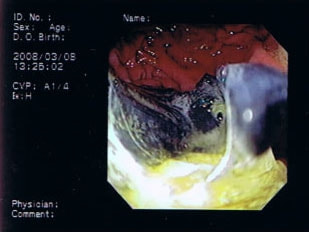

11歳 ミニチュア・ダックス 去勢オス

主訴:焼き鳥の竹串を食べたとの事で来院しました。元気・食欲は問題なく、嘔吐などの症状もありませんでした。便にも竹串が1/3程でているとの事でしたが、全ての竹串が出ていないため、内視鏡検査を実施致しました。

内視鏡検査所見:胃内に竹串の先端部分が残っていたため、異物鉗子にて摘出しました。胃内は、全体的に炎症を伴い、出血している部位も確認されました。摘出後は、胃粘膜保護薬・プロトンプインヒビター(胃薬)の内服2剤ならびに食事療法により経過は良好です。

摘出した竹串

内視鏡下写真

◎竹串誤飲は、異物の1位と言われるほど多く認められています。竹串は、先端が尖っているため消化管穿孔などを起こし、命に関わることもあります。万が一、ご自宅や散歩中に串などを食べてしまった場合は、病院まですぐご連絡下さい。また竹串は、食道を傷つけ・穴をあける恐れなどもあるため無理に吐かせる事は絶対にしないで下さい。本症例は、内視鏡下にて摘出が可能でしたが、状況によっては開腹が必要となる場合もあります。